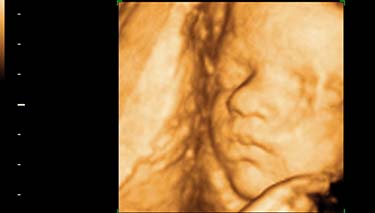

Yes, you ll be amazed at what detail the ultrasound will provide. Be prepared to feel very connected with your baby and perhaps overwhelmed by feelings of love. Many mothers cry when they see their baby in such a realistic way and partners can feel similar feelings as well. For partners who've not experienced pregnancy symptoms first hand, seeing their baby on an ultrasound screen can the first time they really, truly believe the baby exists. Not that this is a commonly discussed issue but it is still a fact.

The ultrasound will pick up images of your baby's organs in a series of cross sections. This can be confusing at first, until you become used to the images and your eyes adjust. Your baby's bones will be white on the screen and the amniotic fluid will appear as black. Their tissues will be grey and have a speckled appearance.